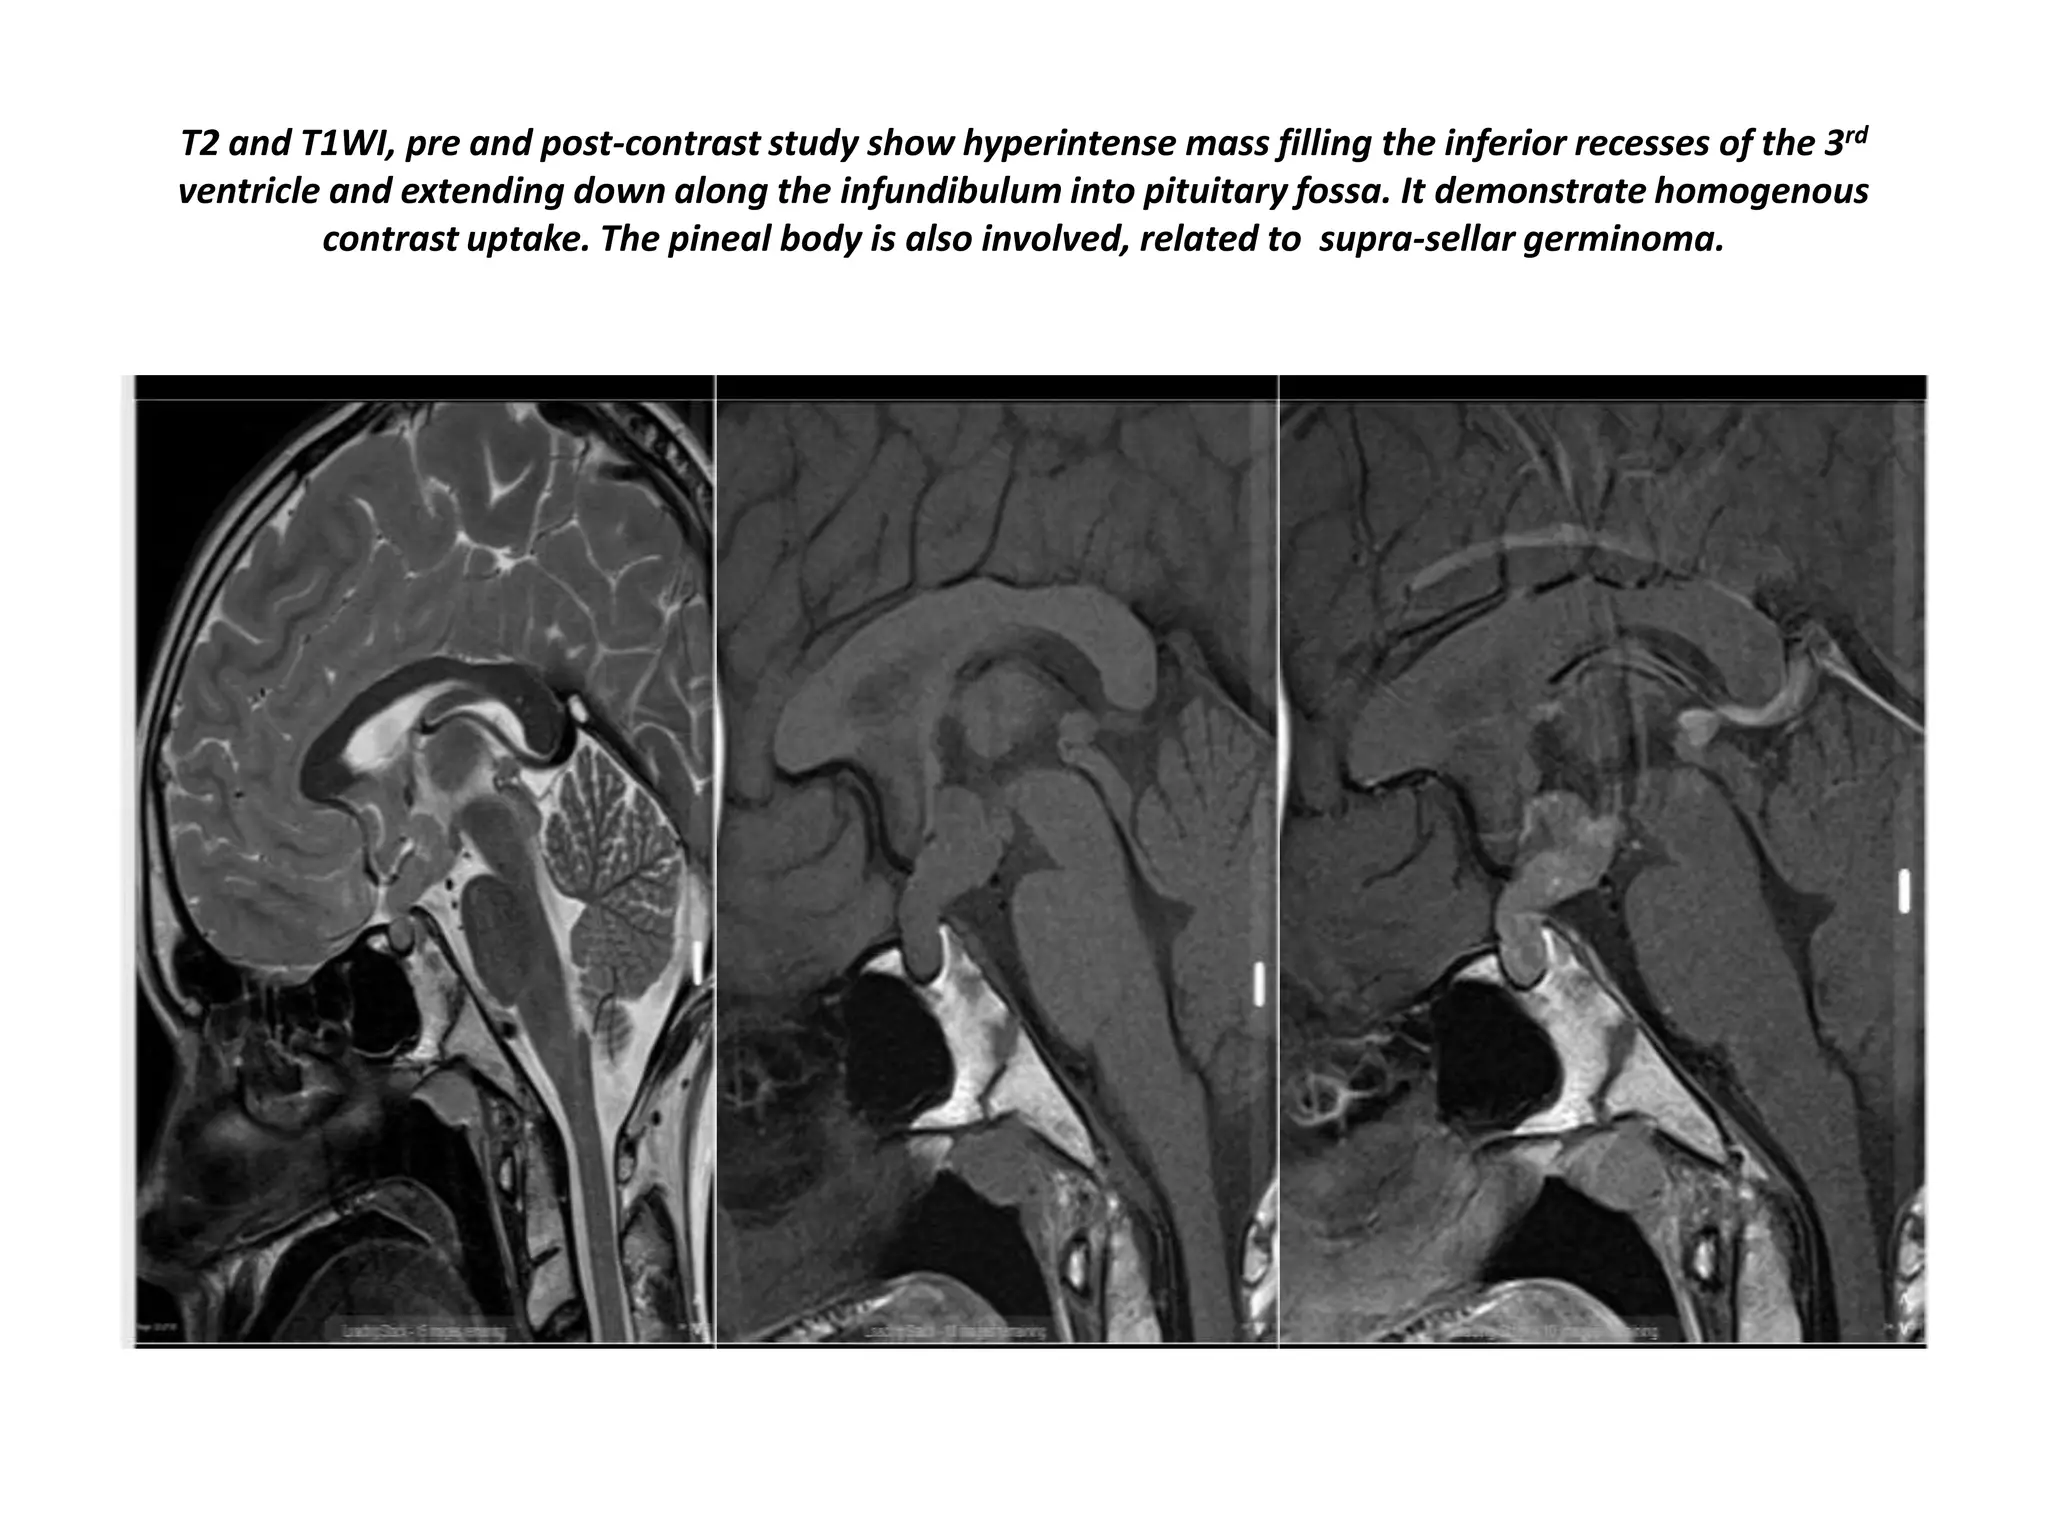

T2 and T1WI, pre and post-contrast study show hyperintense mass filling the inferior recesses of the 3rd

ventricle and extending down along the infundibulum into pituitary fossa. It demonstrate homogenous

contrast uptake. The pineal body is also involved, related to supra-sellar germinoma.

The following case concerns a 9-year-old male with a history of headache, nausea and vomiting. Sagittal T1 images

before and after intravenous contrast show a mass in the midline, on the floor of the third ventricle. The mass

enhances after gadolinium. Continue with next images. Sagittal T2 and T1WI . This is a Germinoma.